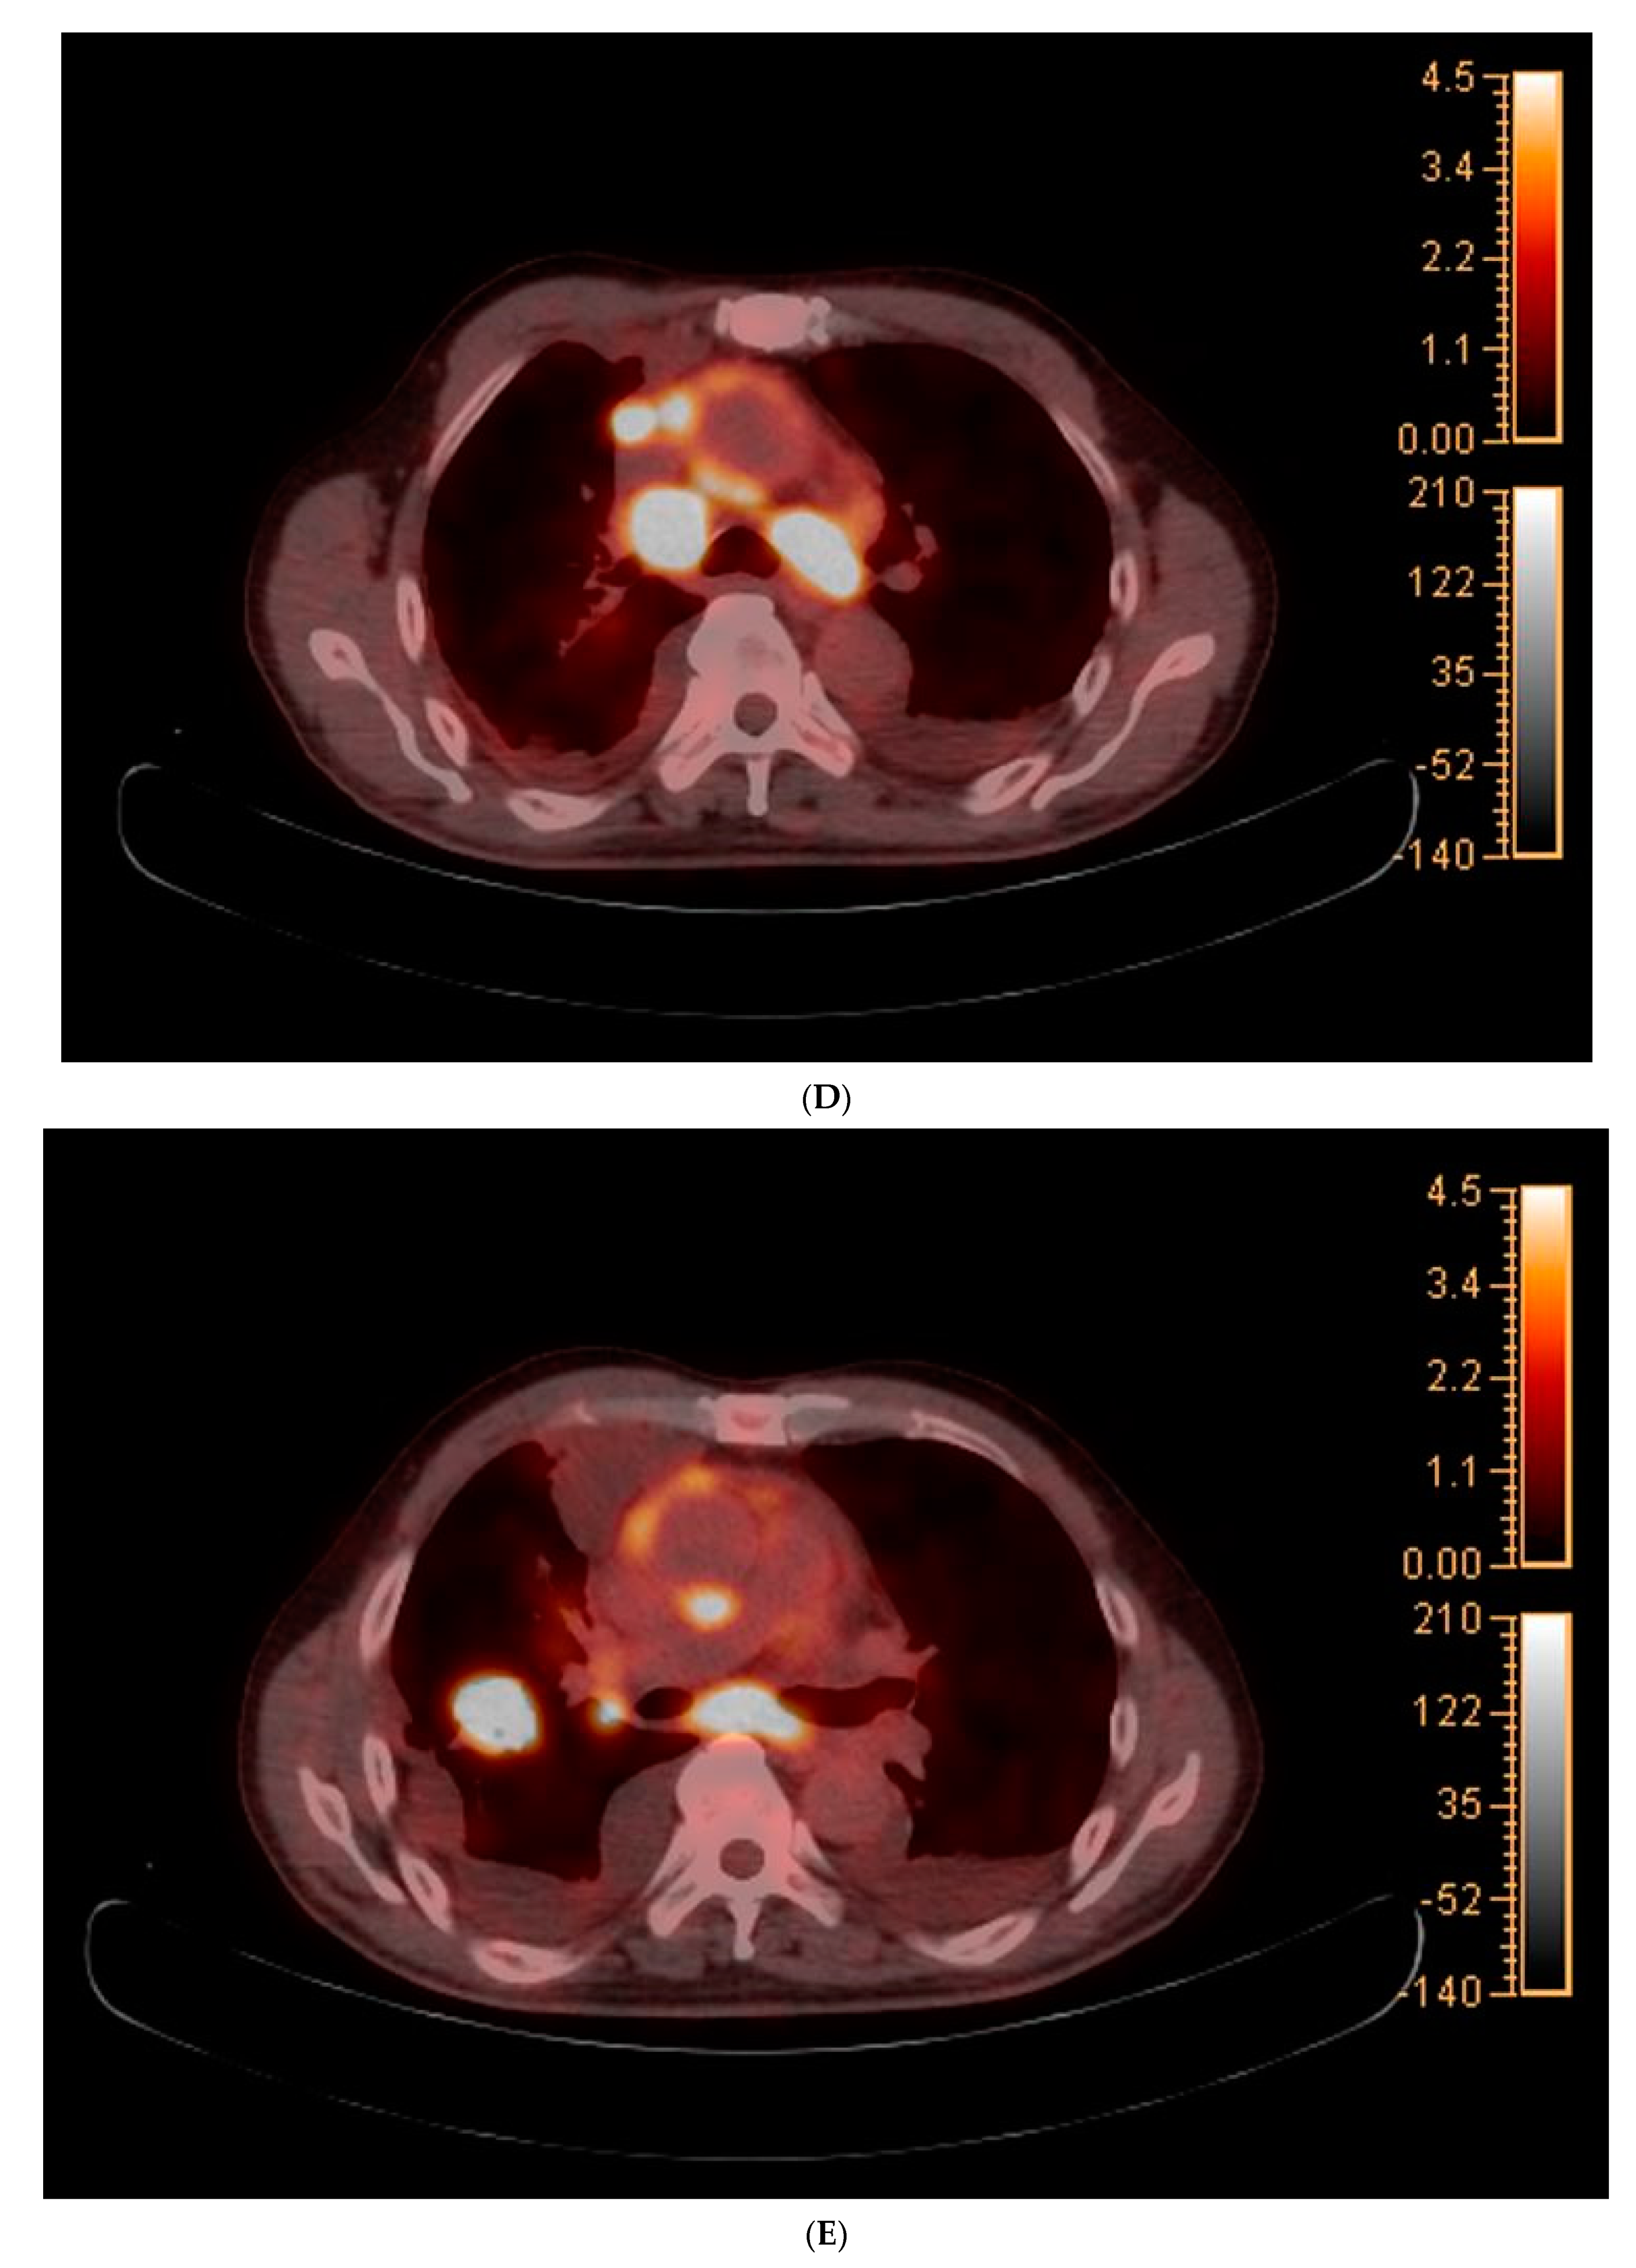

The chest radiography showed a massive right-sided pleural effusion (Figure 1A). Percutaneous catheter drainage was performed for the right-sided pleural effusion. The chest computed tomography showed a 3.3 cm × 3.0 cm mass in the right upper lobe (Figure 1B). The positron emission tomography/computed tomography revealed metastases in the left-sided supraclavicular lymph nodes, multiple bilateral mediastinal lymph nodes, and left scapula (Figure 2). The magnetic resonance imaging of the brain revealed multiple tiny cerebral and right cerebellar metastases (Figure 3). A percutaneous needle biopsy confirmed the diagnosis of lung adenocarcinoma (pT2aN3M1c, stage IVB); the analysis of the right-sided pleural effusion revealed metastatic adenocarcinoma. The genetic analysis revealed an exon 19 deletion in the EGFR gene. The laboratory tests, including the blood cell counts and chemistry, were within the normal ranges prior to treatment initiation. The patient was administered the EGFR-TKI afatinib (40 mg/day) as a first-line chemotherapy.

Figure 2.

(A–E) Positron emission tomography/computed tomography revealed metastases to multiple lymph nodes, includingleft supraclavicular lymph node, bilateral mediastinal areas, and left scapula.